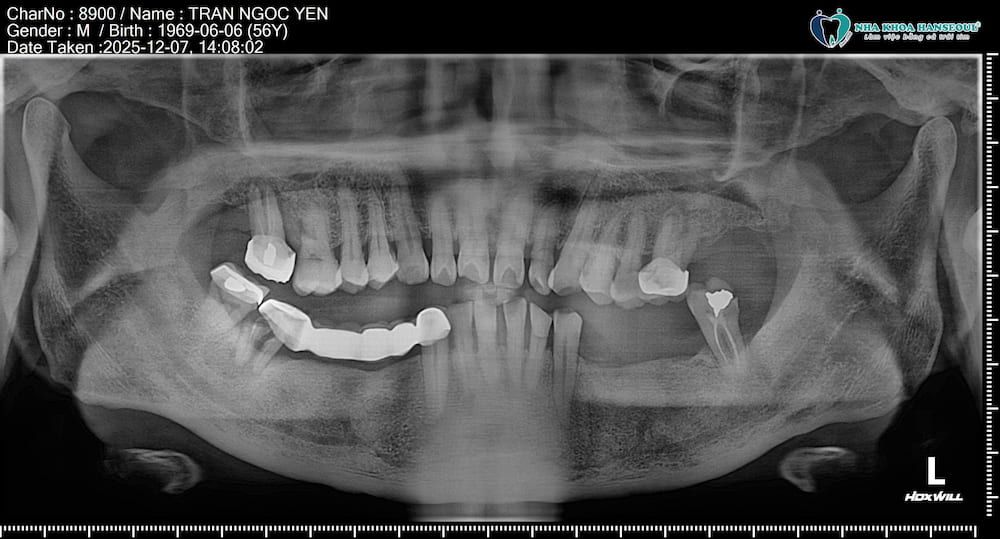

Tình trạng răng miệng trước khi điều trị

Khi đến thăm khám và chụp chiếu tại Hanseoul, thạc sĩ, bác sĩ Trần Việt Hà cho biết, tình trạng của chú Yên được ghi nhận:

Mất răng lâu ngày ở vùng hàm dưới, răng 34, 36, 44, 46, 47 dẫn đến tiêu xương và giảm chức năng ăn nhai rõ rệt.

Các cầu răng giả từng làm trước đây bị gãy tiếp do không còn răng trụ đủ chắc.

Tình trạng mất răng lâu năm kèm theo cầu răng gãy khiến việc ăn nhai của chú ngày càng khó khăn, đồng thời làm tăng nguy cơ tiêu xương và sai khớp cắn nếu không can thiệp kịp thời.